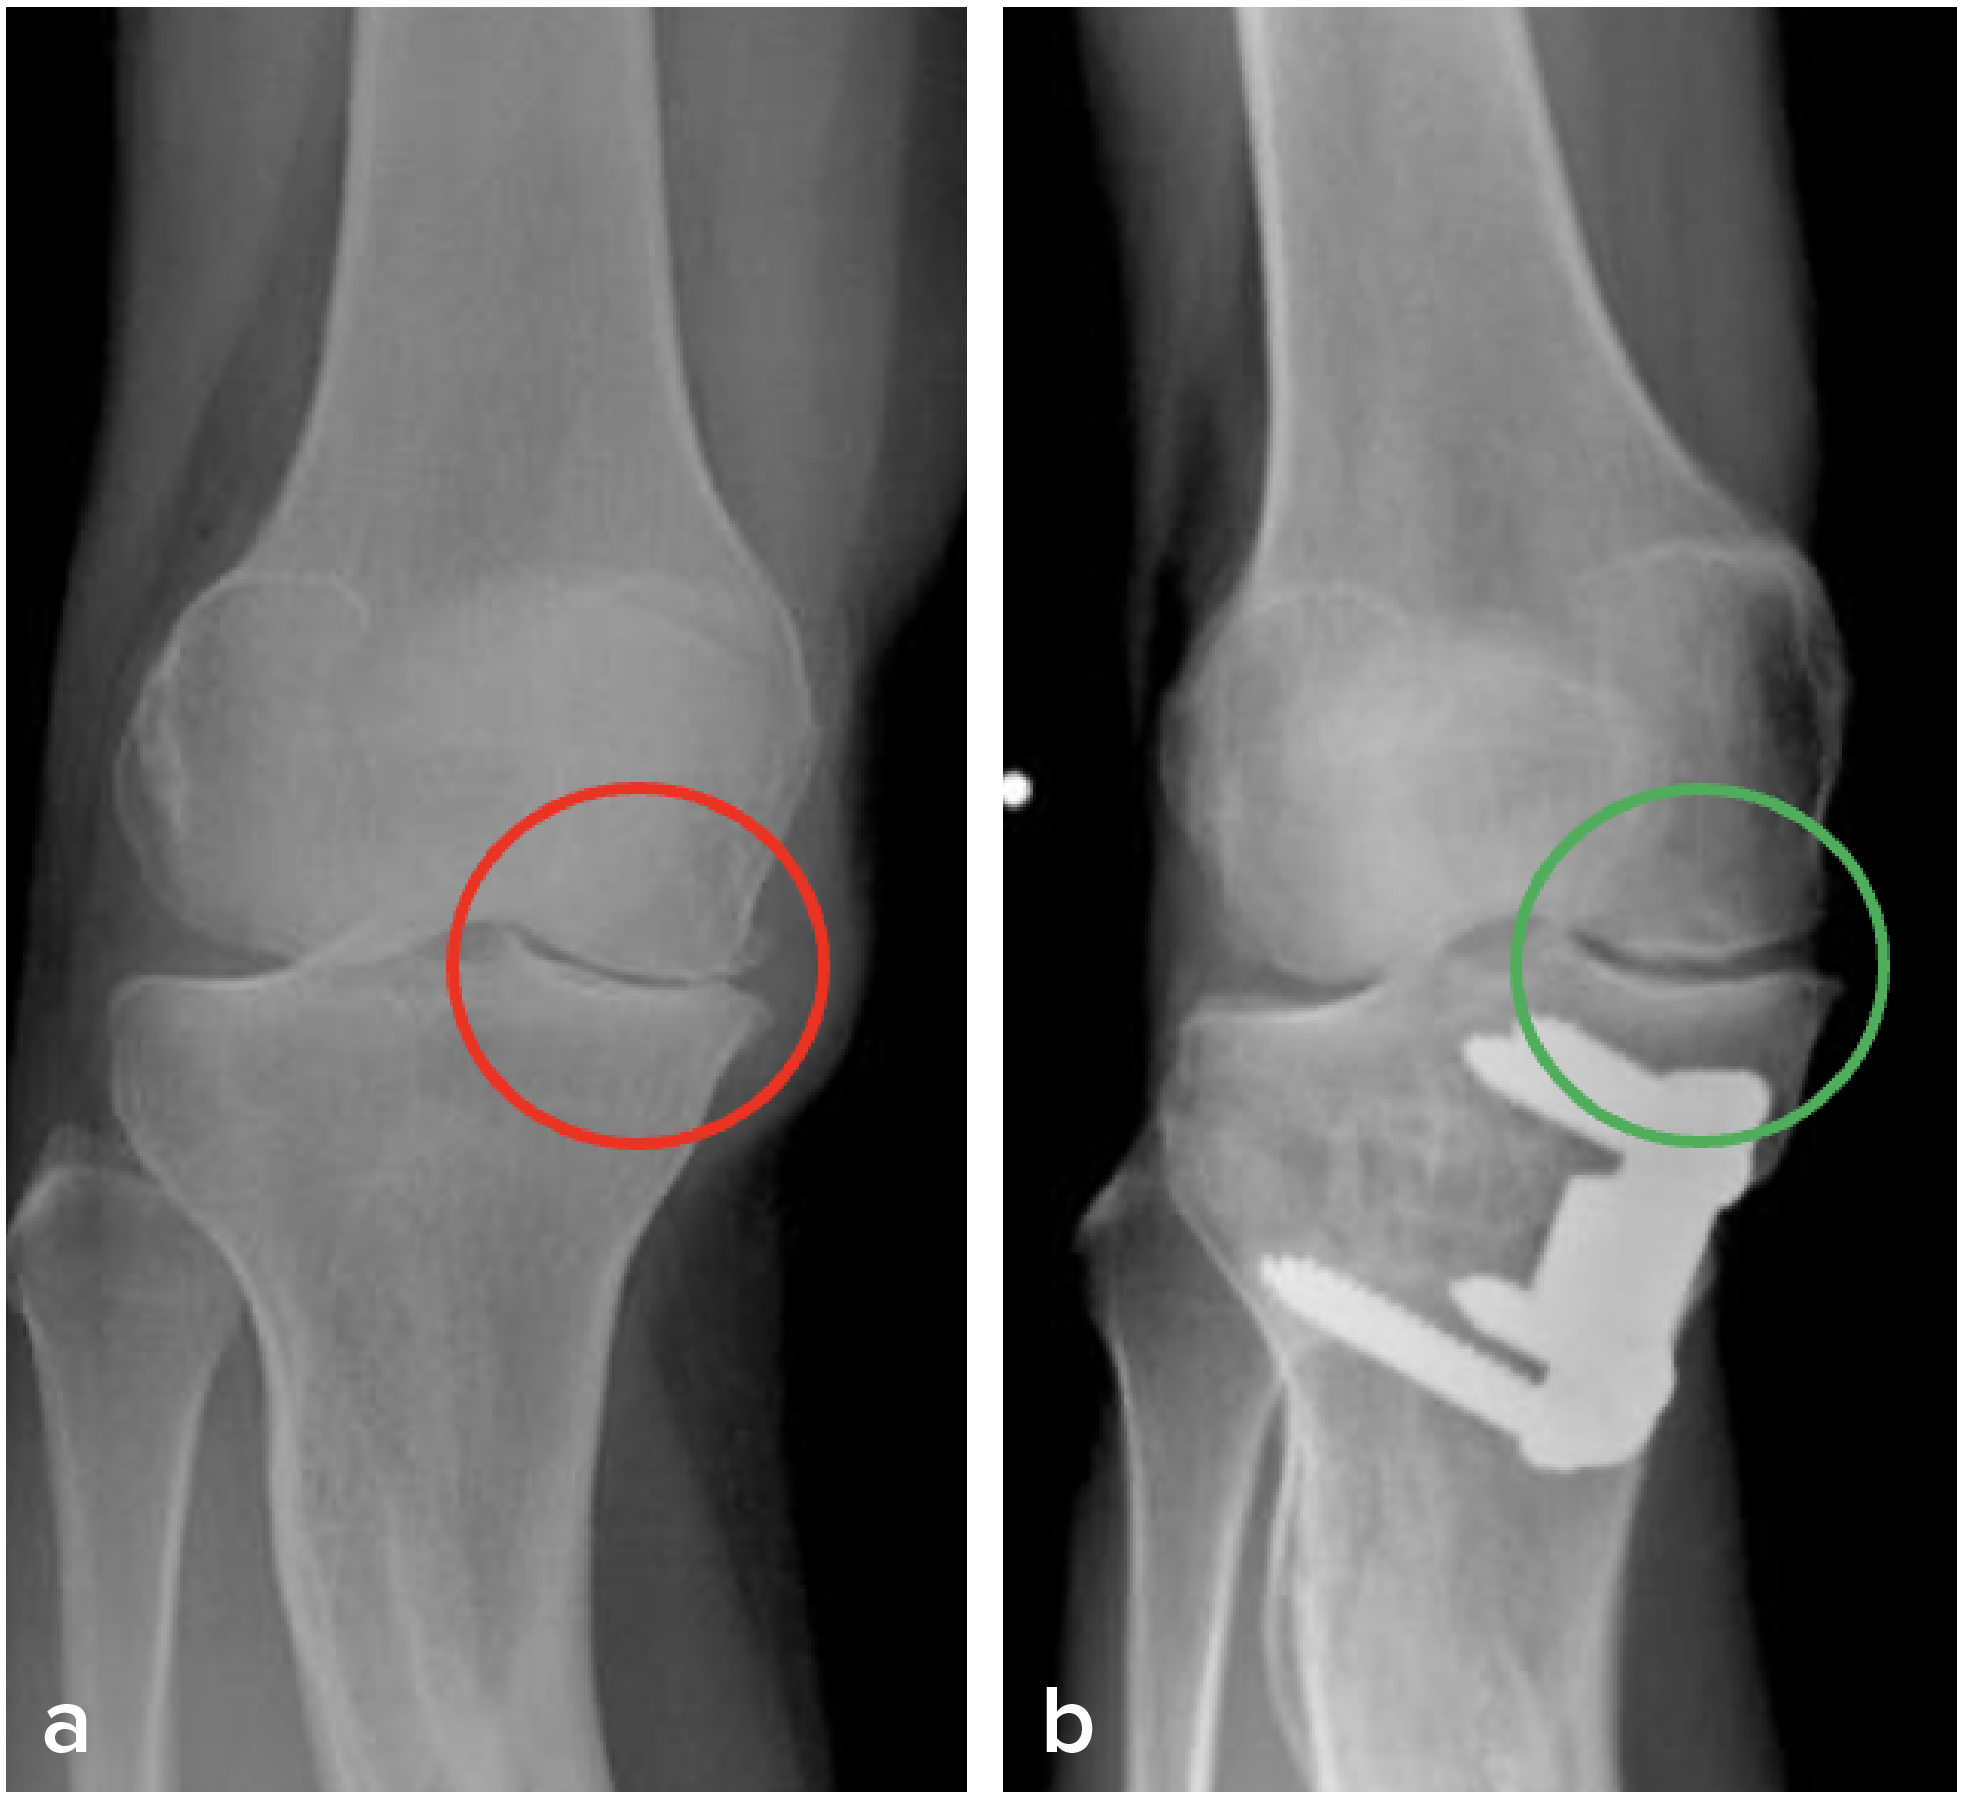

HTO is nowadays regarded more as a buying-time procedure before TKA. But that grim prospect brightens up when HTO is performed concomitantly with ACRFP. Our patients who received HTO and ACRFP together have enjoyed good long-term results as shown in Figure 4, which is an example of the reversal of the degeneration process after receiving ACRFP and HTO: a, AP standing view of a 45-year-old female patient having stage IV traumatic OA over the medial compartment of her right knee; b, 10 years later, an X-ray image shows obvious cartilage regeneration.